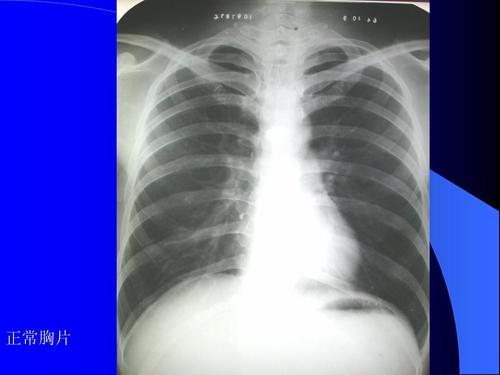

胸片正常图片

正常胸片图片图解

正常胸片和肺炎胸片图

肺部正常胸片影像图片

正常肺部胸片

正常人胸片图片

正常人的肺部胸片图

正常肺部胸片正常人

胸片正常图片女性

正常胸片影像图片